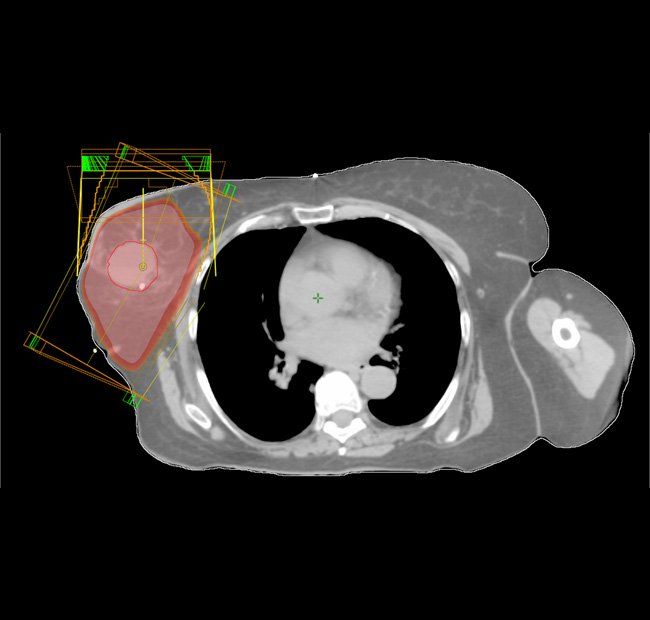

According to Wobb, breast-conserving therapy consisting of lumpectomy and radiotherapy is the standard of care for early-stage breast cancer. Accelerated partial breast irradiation is considered one of the methods for delivering radiotherapy in appropriately selected patients.

Therefore, Wobb and her colleagues developed a nomogram that takes into account clinicopathologic features that helps predict risk for locoregional recurrence in patients undergoing accelerated partial breast irradiation.